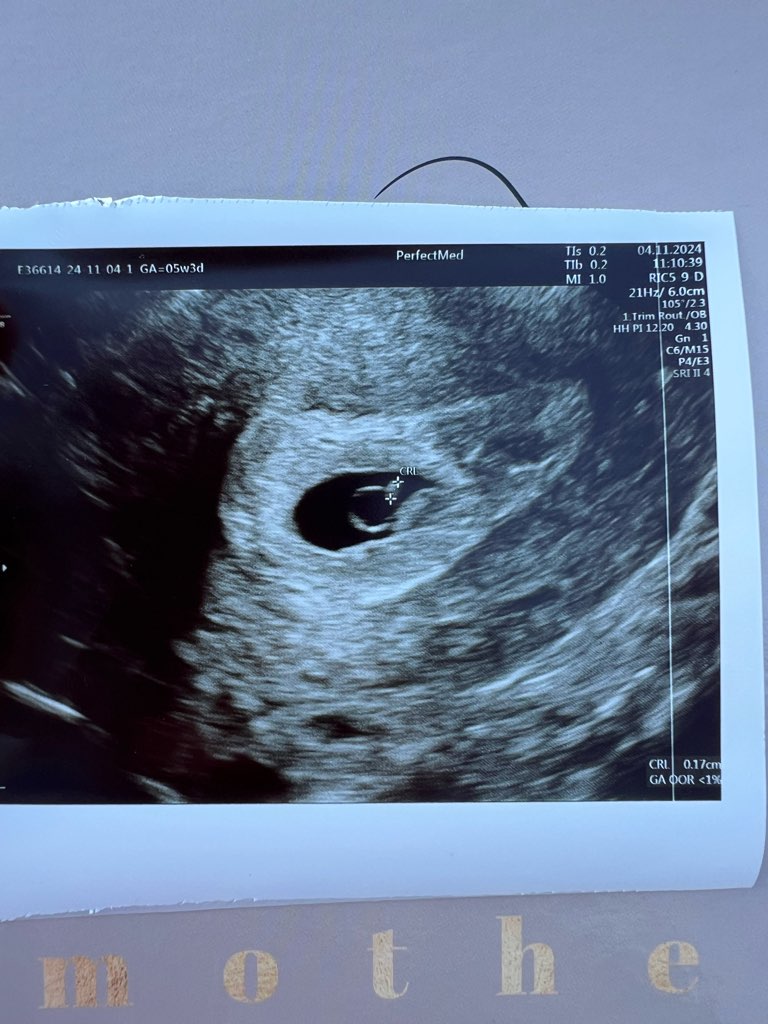

Ale z dobrych wieści to mamy aż 1,7mm człowieka :)

• IMG_0272.jpeg

IMG_0272.jpeg

124,2 KB · Wyświetleń: 117